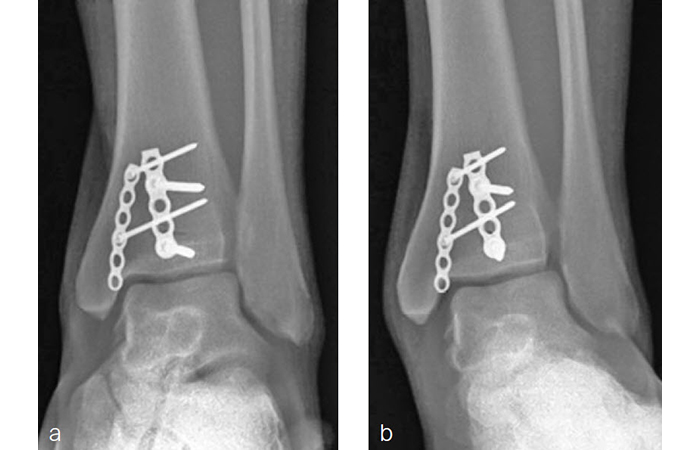

A 34-year-old woman was injured while riding a motor scooter sustaining an ankle fracture with associated syndesmotic injury (Fig 6a). The fibula was reduced anatomically and stabilized with a 1/3 tubular plate (Fig 6b). The unstable syndesmosis was reduced and provisionally stabilized with a K-wire and clamp (Fig 7) before FIBULINK Implant System implantation (Fig 8). The patient had an uneventful recovery (Fig 9).